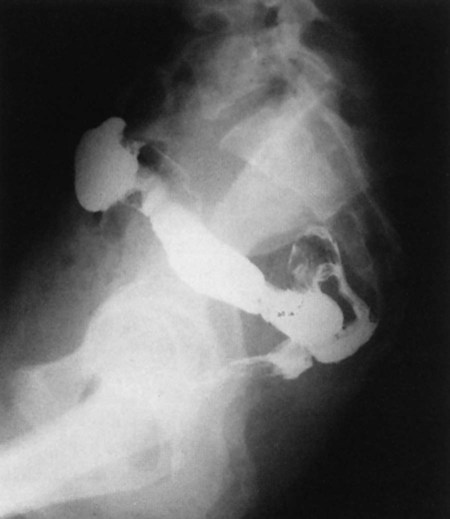

The radiographic procedure designed to study the large intestine is most commonly termed a barium enema. Alternative designations include BE, BaE, and lower GI series. Fig. 13-3 shows a large bowel or colon filled with a combination of air and barium, referred to as a double-contrast barium enema. Note: This patient has situs inversus, in which abdominal and thoracic organs are reversed from their normal orientation within the body.

inches) of large intestine is constricted to form the anal canal. The anal canal terminates as an opening to the exterior, the anus. The rectum closely follows the sacrococcygeal curve, as demonstrated in the lateral view in Fig. 13-11.

The rectal ampulla is a dilated portion of the rectum located anterior to the coccyx. The initial direction of the rectum along the sacrum is inferior and posterior. However, in the region of the rectal ampulla, the direction changes to inferior and anterior. A second abrupt change in direction occurs in the region of the anal canal, which is directed again inferiorly and posteriorly. Therefore, the rectum presents two anteroposterior curves. This fact must be remembered when a rectal tube or enema tip is inserted into the lower gastrointestinal tract by the technologist for a barium enema procedure. Serious injury can occur if the enema tip is forced at the wrong angle into the anus and anal canal.